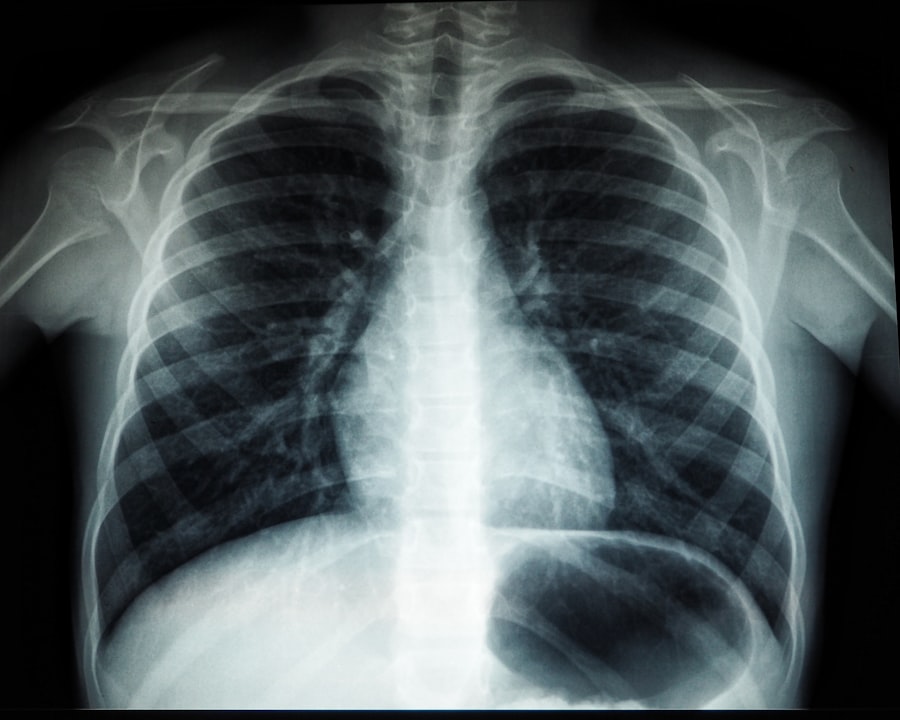

If you experience persistent respiratory symptoms or notice changes in your breathing patterns, seeking medical intervention is essential. Early detection and treatment of respiratory issues can prevent complications and improve outcomes significantly. Your healthcare provider may recommend diagnostic tests such as pulmonary function tests or imaging studies to assess your lung health accurately.

Common tests include spirometry, which measures the amount and speed of air a person can exhale, and pulse oximetry, which checks oxygen levels in the blood. More detailed tests may be done depending on symptoms.